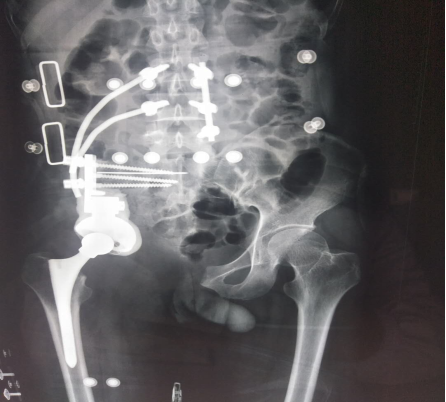

患者33岁男性,髋部疼痛不适3月余入院,经检查及病理提示骨盆I+Ⅱ+Ⅲ区巨大恶性骨肿瘤。骨盆的恶性肿瘤,往往就诊时肿瘤已经发展了相当长的时间,而肿瘤巨大、术中出血多、局部解剖结构复杂等因素使得手术难度及风险增高。早年对骨盆恶性肿瘤的治疗,半骨盆截肢术是骨盆恶性肿瘤的主要治疗方式。但患者所承受的心理压力巨大,面对肢体残缺所引起的恐慌使其拒绝接受治疗,尤其对于年轻患者。保肢术的开展及应用为这些患者带来希望,但手术难度极大,不易达到安全的外科边界。胡勇教授团队根据患者病情,制定精细手术方案,多套治疗及手术预案,于我科行3次化疗,缩小肿瘤反应区。积极完善术前准备工作后于患者行骨盆I+Ⅱ+Ⅲ区巨大骨肉瘤行腹主动脉球囊阻断+半骨盆肿瘤切除+腰骶椎骨盆重建+髋关节置换术,术中既完整切除了巨大骨盆肿瘤,又重建了腰骶椎及骨盆、髋臼的稳定性,最大程度的保留肢体功能,患者术后恢复良好,顺利出院。

胡勇教授指出,骨盆肿瘤的规范化治疗中,肿瘤的完整切除及功能重建在其治疗中占重要地位,由于骨盆位置深在,血管神经、肠道泌尿道毗邻,骨盆肿瘤的完整切除手术难度极大,技术要求高。同时,此部位是人体最重要的生物力学枢纽,对于肢体的重建要求高,难度大。完整的半骨盆切除后,准确重建肢体长度、外形、关节匹配关系等,对患者的肢体结构和功能的回复意义极其重大。